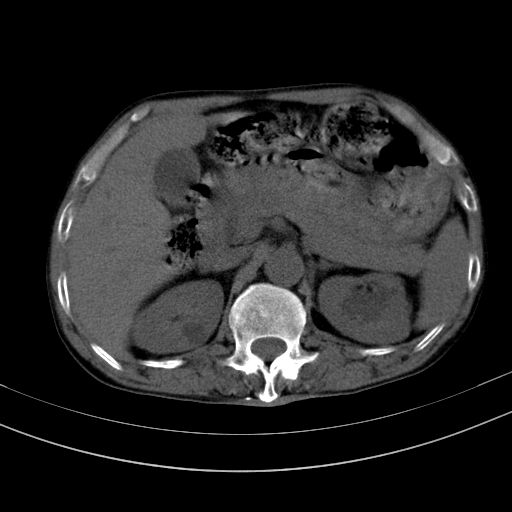

以下是引用dyqct在2010-1-9 17:56:00的发言:[br]考虑:1.双肾囊肿,左肾积水结石、旋转不良。[br] 2.右侧腹直肌血肿或纤维瘤。[br]肠道准备不好。做个增强。